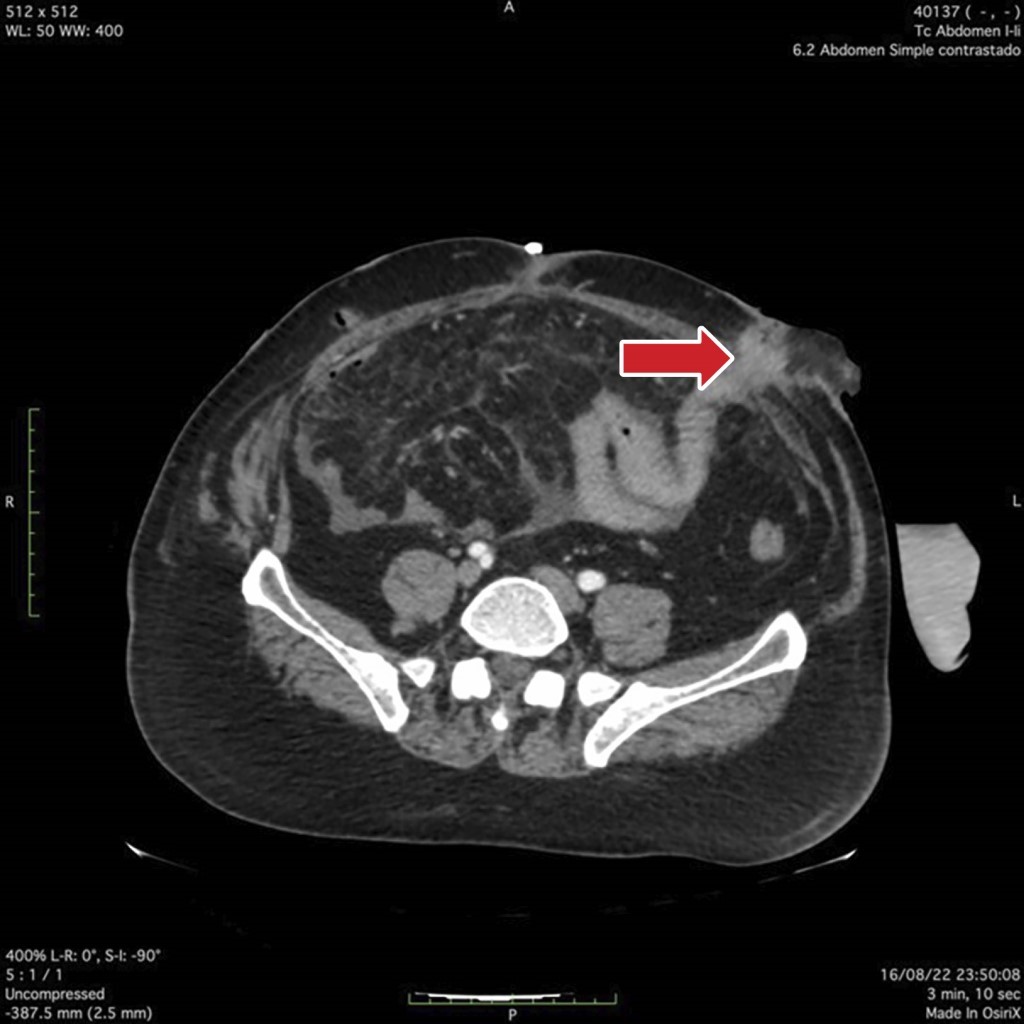

Laboratorios a su ingreso: tiempo de protrombina (TP) 17.2 segundos, índice internacional normalizado (INR, por sus siglas en inglés) 1.5, tiempo parcial de tromboplastina (TTP) 27.9 segundos; proteína C reactiva (PCR) 8.8 mg/dl, = velocidad de sedimentación globular (VSG) 50 mm/h, procalcitonina 0.63 ng/ml; leucocitos 10.66 × 109/l, neutrófilos 8.57, hemoglobina (HB) 9.8 g/dl, hematocrito (Hto) 31.1%, volumen corpuscular medio (VCM) 100.5 fl, hemoglobina corpuscular media (HCM) 31.6 pg, plaquetas 485,000/mm3; bilirrubina total (BT) 1 mg/dl, albúmina 3.3 g/dl, proteínas 5.4 g/dl, globulina 2.1 g/dl; sodio (Na) 146 meq/l, potasio (K) 4 meq/l, cloro (Cl) 111 meq/l, calcio (Ca) 7.5 meq/l, fósforo (P) 2.8 meq/l, magnesio (Mg) 1.8 meq/l, nitrógeno ureico en sangre (BUN) 12 meq/l, creatinina (Cr) 0.55 mg/dl. Tomografía sin evidencia de colecciones. Se realiza manejo y control de sepsis, así como desequilibrio hidroelectrolítico y se realiza soporte nutricional con nutrición parenteral al 100%; a los 15 días se decide reintervenir encontrando abdomen congelado; se realiza disección a través del epiplón hasta encontrar asa de intestino delgado, se coloca sonda Foley de 18 Fr con técnica de Witzel. Se realiza paso de medio de contraste, se localiza sitio de inserción de yeyunostomía en yeyuno (Figura 2), por lo cual se realiza inicio de nutrición por la misma, se inicia dieta al 100% vía oral con recolección de quimo y autotrasplante por el mismo paciente (Figura 3). A las dos semanas se realiza balance nitrogenado encontrándolo positivo, por lo que se decide su egreso y manejo ambulatorio después de 36 días de estancia hospitalaria. A los siete meses del egreso se realiza protocolo de reconexión sin complicaciones, con egresó a los siete días con recuperación total.

Figura 2